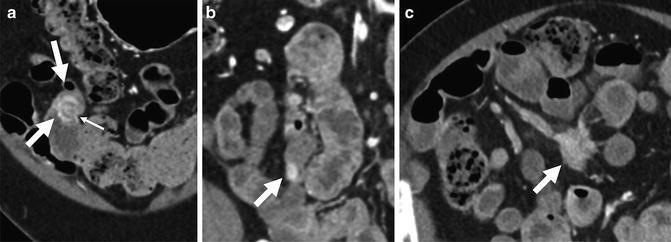

- опухоли тонкой кишки (лимфома, ГИСО, карциноид, рак тонкой кишки, метастазы)

Это современный способ диагностики тонкого кишечника, основанный на компьютерной томографии. При этом мы получаем послойные изображения органа после того, как пациент выпивает специальный раствор в клинике перед исследованием. Действие препарата заключается в удерживании воды в просвете кишечника, что предотвращает ее всасывание.

Метод позволяет эффективно оценить состояние стенки кишечника и выявить внутренние изменения, а также ответить на множество диагностических вопросов.

Исследование назначается при подозрении на опухоли тонкой кишки или болезнь Крона, а также для диагностики целиакии.